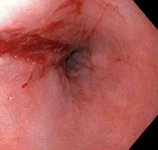

Bleeding Mallory Weiss Tear viewed on retroflexion

From the personal collection of Douglas Adler; used with permission